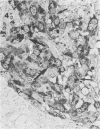

Granulomatous lesions of bovine paratuberculosis contained ferritin, lactoferrin, and a small amount of transferrin, as demonstrated by the immunohistochemical method. Macrophages in the normal bovine ileum did not contain lactoferrin and transferrin; however, ferritin was found in individual macrophages of Peyer's patches. These results may help elucidate the relationship between intracellular growth of Mycobacterium paratuberculosis and the presence of iron-binding proteins in the granulomas.